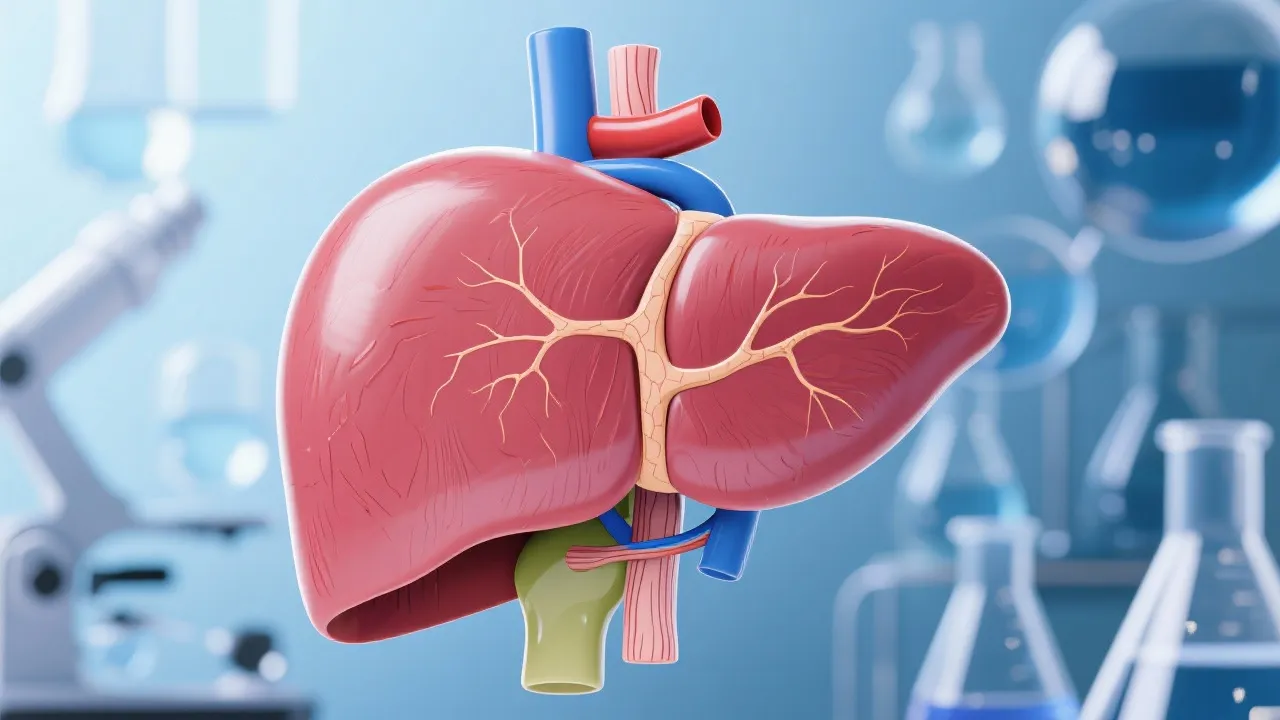

Non-Alcoholic Fatty Liver Disease (NAFLD) is an alarming health issue characterized by fat accumulation in the liver in individuals who consume little to no alcohol. This burgeoning condition is often linked to an increase in lifestyle-related factors, particularly obesity, poor diet, and sedentary habits, leading to a global epidemic. NAFLD can progress to more severe liver conditions such as non-alcoholic steatohepatitis (NASH), fibrosis, and cirrhosis. Globally, it affects a significant proportion of the population, with estimates suggesting that over 25% of adults in the United States and 10-30% of adults worldwide may be affected by this condition. It is closely associated with metabolic disorders like obesity and diabetes. Despite its prevalence, effective medical therapies remain elusive, primarily due to incomplete understanding and complexity of its pathogenesis. Consequently, it poses a substantial burden on healthcare systems and highlights the urgent need for effective diagnostic and therapeutic options.

The urgent need for viable NAFLD treatments has spurred significant research into developing reliable NAFLD models. In recent years, an increasing number of studies have focused on accurately mimicking the disease process, which is crucial for potential therapeutic interventions. These models are essential in simulating human disease states, thereby assisting scientists in understanding disease mechanisms and assessing the efficacy of potential therapeutic agents. The development of these models can provide a platform for testing new drug candidates, allowing researchers to measure their effects on the progression of NAFLD and its complications, thereby speeding up the drug discovery pipeline.

Several types of models are implemented in current research to study NAFLD. Each model type offers unique insights, benefiting various aspects of drug discovery. Understanding the specific applications, limitations, and strengths of these models is integral to advancing treatment options for NAFLD. In vitro models, like hepatocyte cultures, provide insights into cellular responses to drugs and pathological changes. However, they lack the complexity of human liver architecture, and while they can be informative, they might not always accurately predict human responses to treatment.